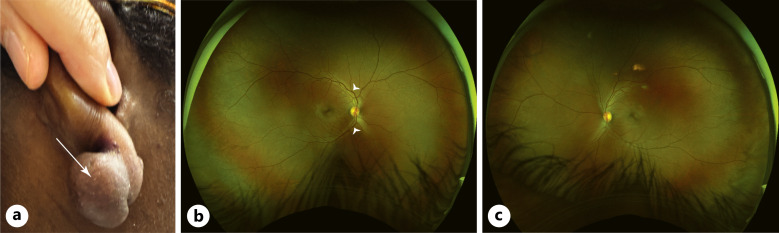

简介:局部曲安奈德是一种广泛用于瘢痕性皮肤疾病(如瘢痕疙瘩)的治疗方法,已知如果在眼周区域使用曲安奈德会导致视网膜血管并发症。病例介绍:一名32岁女性因瘢痕瘤毁损,在右耳垂注射曲安奈德皮质类固醇(TAC)后,右眼出现突发性短暂性视力下降和迟发性缓慢消退的视力丧失。临床表现为视网膜分支动脉闭塞并伴有视网膜中央静脉闭塞。进入视网膜循环的TAC颗粒与视网膜分支动脉的血栓栓塞闭塞和随后的视网膜中央静脉阻塞有关。结论:该病例应提醒临床医生,由于颈外动脉和颈内动脉循环之间有丰富的吻合,在头面区域注射皮质类固醇总是存在视网膜血管闭塞的潜在危险。

Case presentation: A 32-year-old female experienced a prompt onset transient vision decrease and a delayed onset, slow-resolving vison loss in the right eye (OD) following the last of a series of triamcinolone acetonide corticosteroid (TAC) injections in her right earlobe for a disfiguring keloid. Clinically, she developed a branch retinal arterial occlusion accompanied by features of a central retinal vein occlusion. The TAC particles that entered the retinal circulation are implicated in the thrombo-embolic occlusion of the branch retinal artery and subsequent blockage of the central retinal vein.